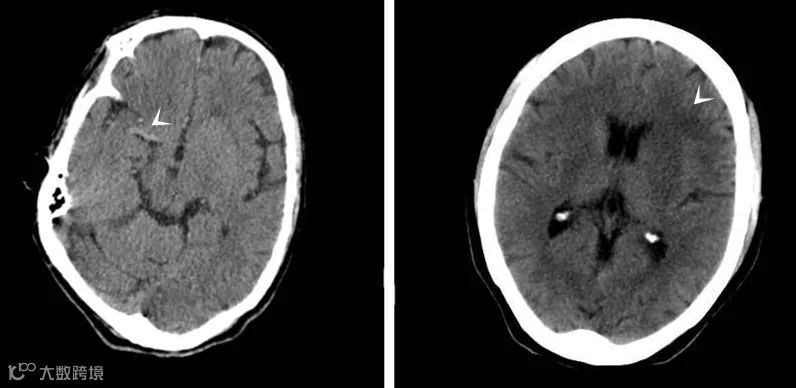

低密度改变并不是急性缺血性脑卒中的唯一征象,在某些情况下,高密度动脉征可能为缺血性脑卒中在平扫CT图像上最早或唯一的征象,如上图△左。

该征象在大脑中动脉较为常见,对于缺血性脑卒中诊断的特异性可高达90%-100% ,但敏感度低于30%。